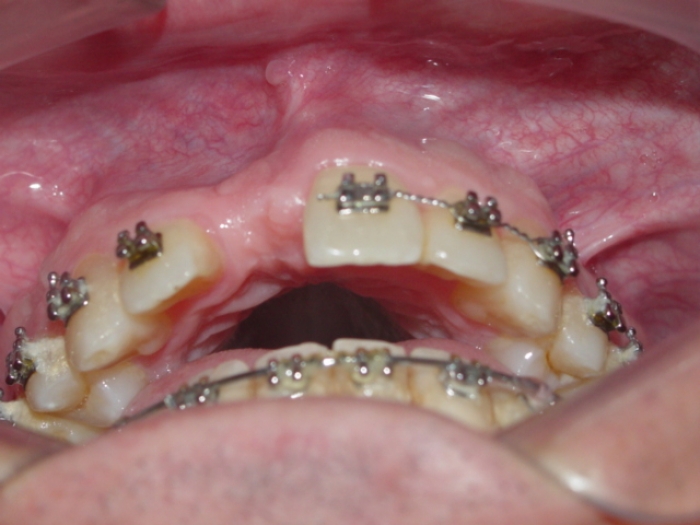

Imagem inicial